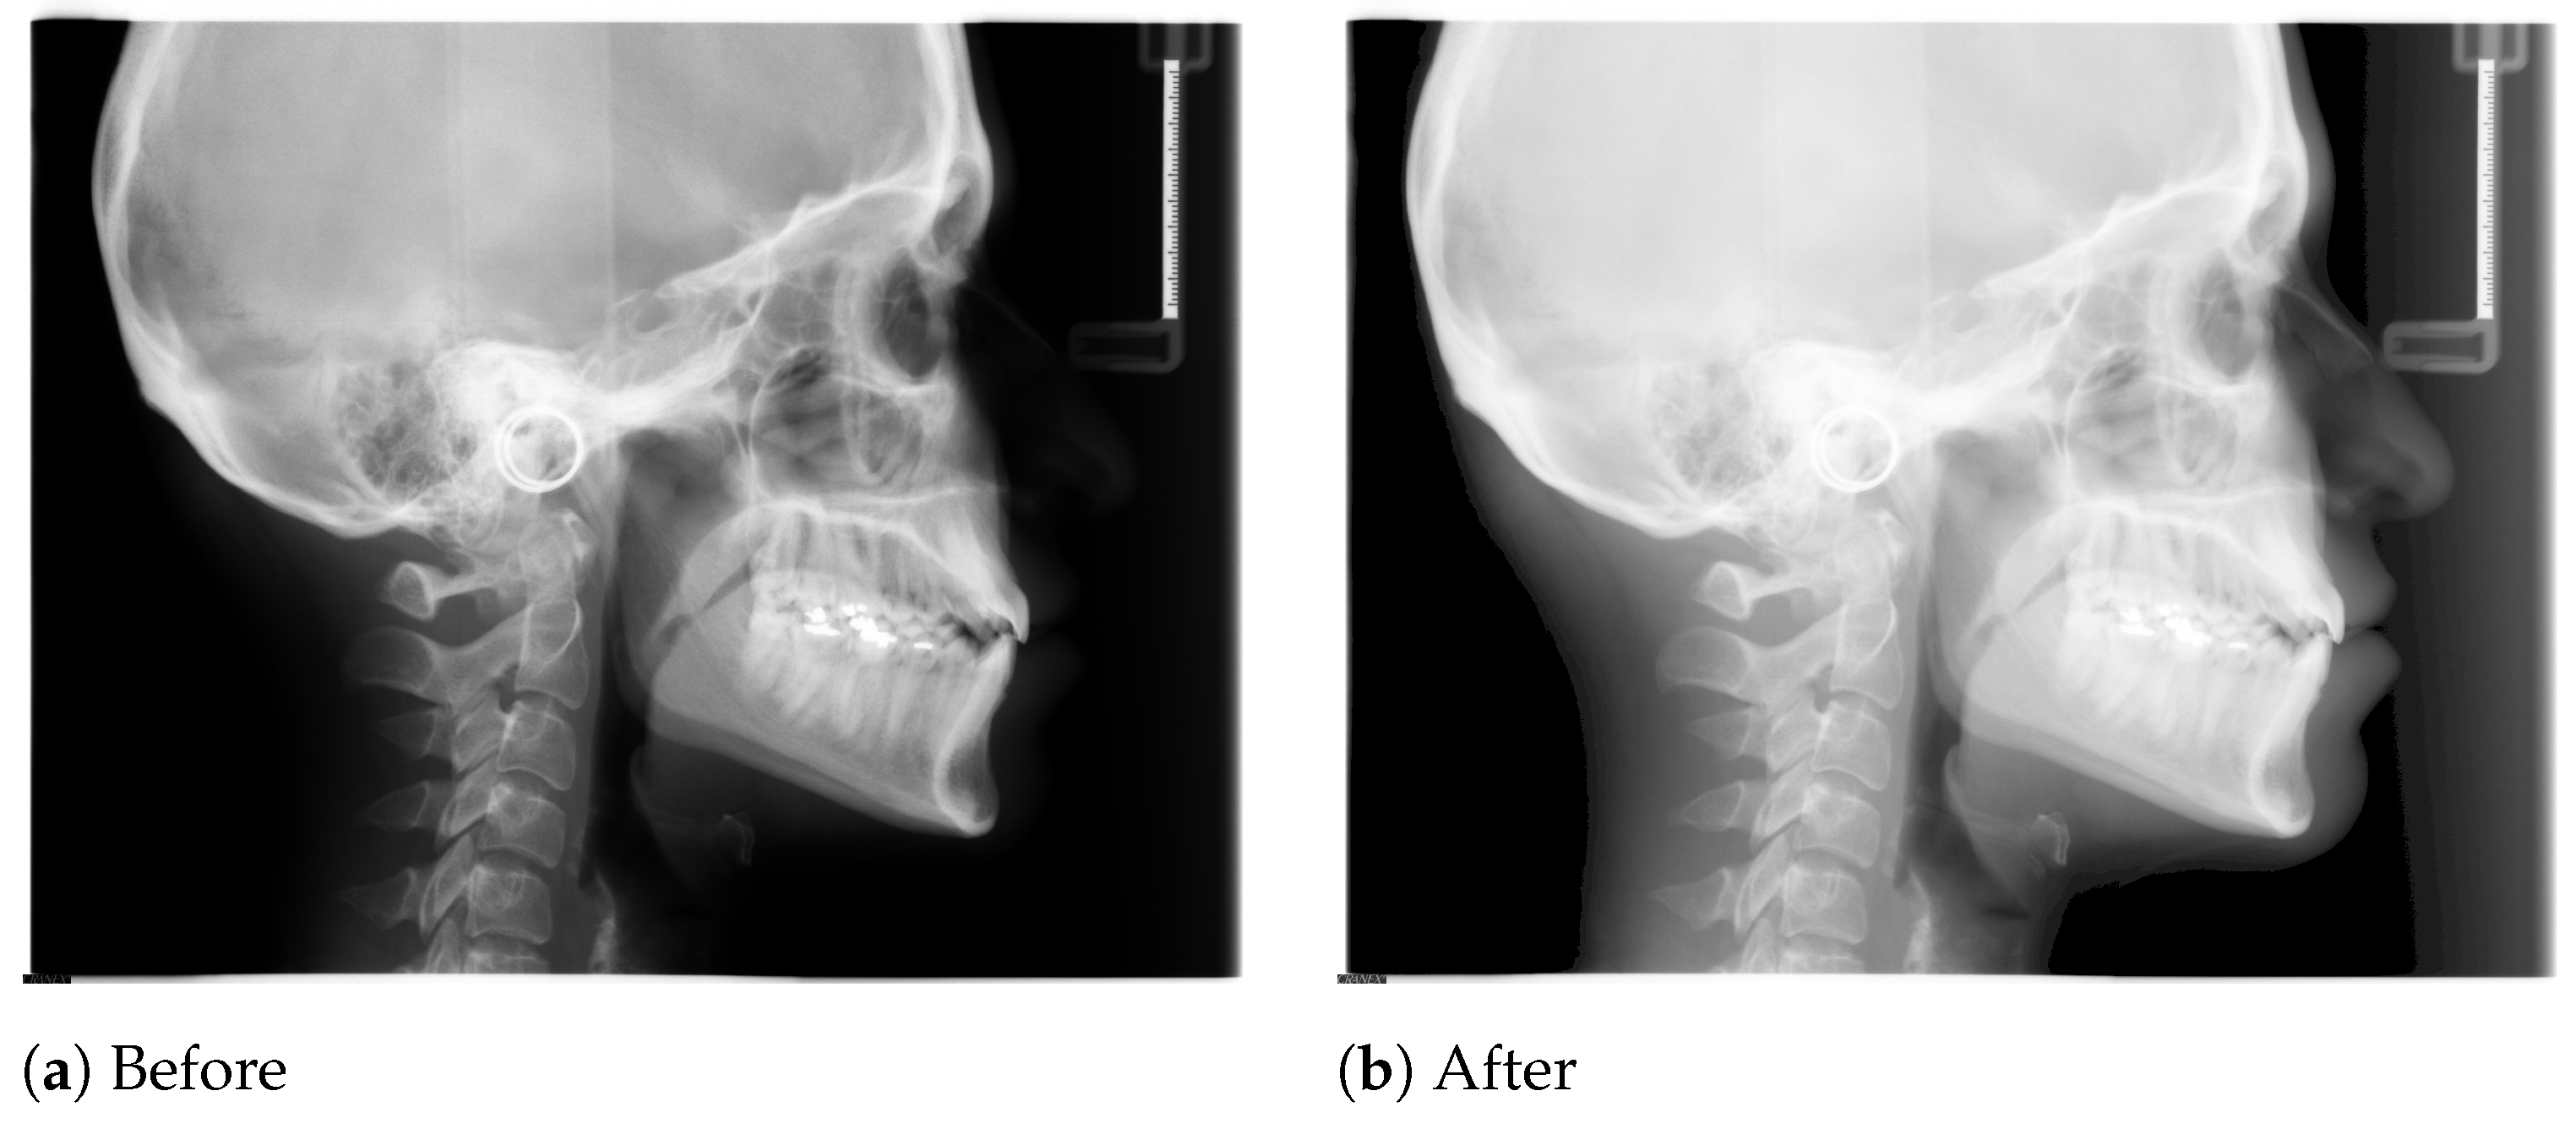

The borders of the soft tissue in the initial X-ray images are not clearly visible due to poor contrast, and hence we need to apply some preprocessing steps, i.e., to use the gamma correction method to sharpen and increase the contrast of the borders of the soft tissue.

In Figure 1, we show a sample X-ray image before and after applying the gamma correction. It is clear that after applying the gamma correction, the soft tissue borders are now visible for further usage. In our tool, we first preprocess all X-ray images using the gamma correction before performing actual annotations.

Figure 1. Effect of gamma correction of a sample X-ray image.